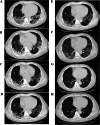

Methods: A prospective cohort study of patients with COVID-19 from the First Affiliated Hospital, Zhejiang University School of Medicine was conducted, with assessments of chest CT during hospitalization and at 2 weeks, 1 month, 3 months, 6 months, and 1 year after hospital discharge. Risk factors of residual CT opacities and the influence of residual CT abnormalities on pulmonary functions at 1 year were also evaluated.

Results: A total of 41 patients were followed in this study. Gradual recovery after hospital discharge was confirmed by the serial CT scores. Around 47% of the patients showed residual aberration on pulmonary CT with a median CT score of 0 (interquartile range (IQR) of 0-2) at 1 year after discharge, with ground-glass opacity (GGO) with reticular pattern as the major radiologic pattern. Patients with residual radiological abnormalities were older (p = 0.01), with higher rate in current smokers (p = 0.04), higher rate in hypertensives (p = 0.05), lower SaO2 (p = 0.004), and higher prevalence of secondary bacterial infections during acute phase (p = 0.02). Multiple logistic regression analyses indicated that age was a risk factor associated with residual radiological abnormalities (OR 1.08, 95% CI 1.01-1.15, p = 0.02). Pulmonary functions of total lung capacity (p = 0.008) and residual volume (p < 0.001) were reduced in patients with residual CT abnormalities and were negatively correlated with CT scores.

Conclusion: During 1-year follow-up after discharge, COVID-19 survivors showed continuous improvement on chest CT. However, residual lesions could still be observed and correlated with lung volume parameters. The risk of developing residual CT opacities increases with age.